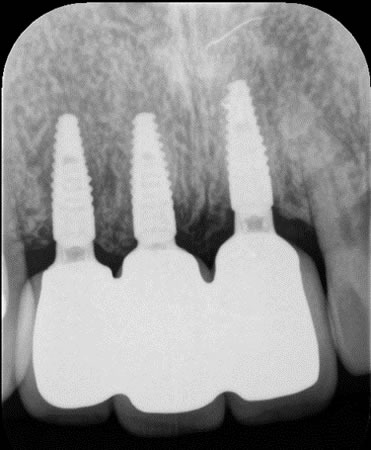

先日、県北の同窓生の先生から紹介いただいた前歯のインプラントの患者さんの治療が終わり、紹介いただいた先生から連絡がありました。

前歯の歯がなく、入れ歯を使用しているのですが、固定式(インプラント)を希望され紹介いただきました。

■治療後